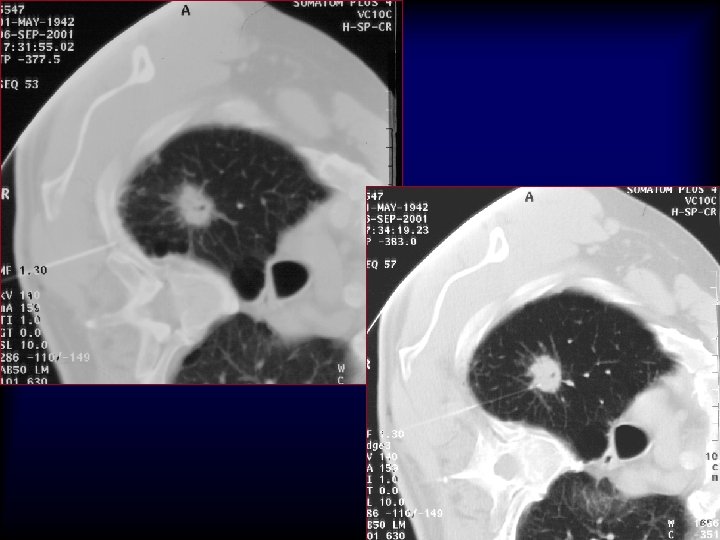

20 G/9 cm/10 T x 25 x 40 x 200 5 mm Adenocarcinoma H&E